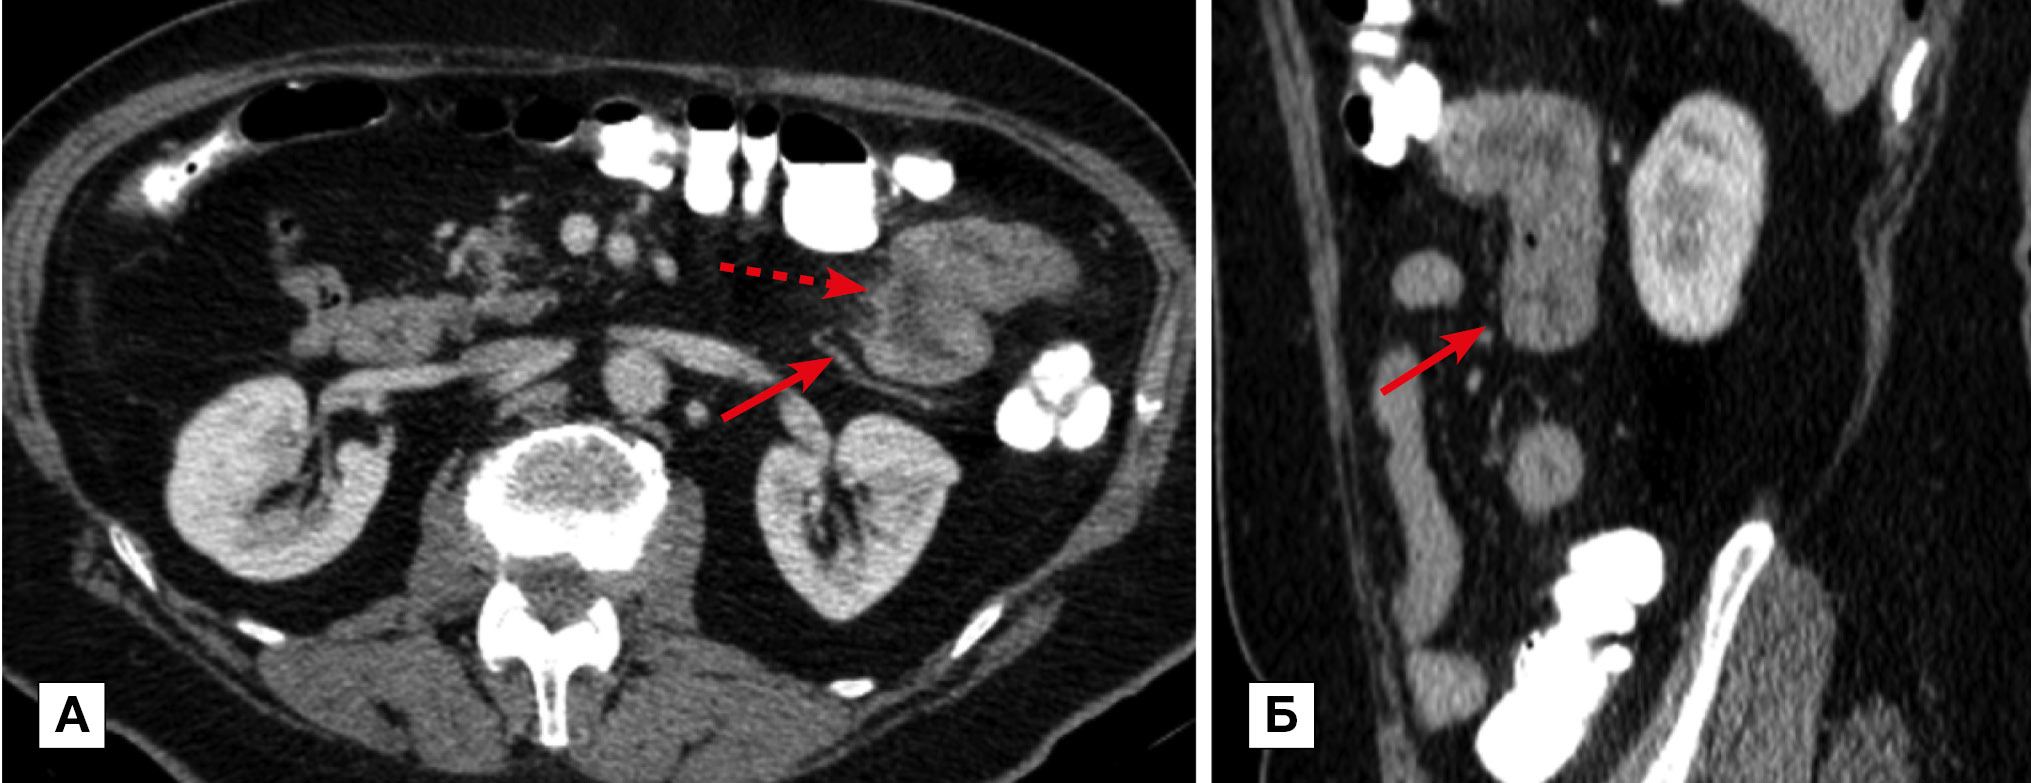

Рис. 4. Больная, 36 лет. МСКТ: В-клеточная лимфома, инфильтративная форма

Примечание. В 4-й части двенадцатиперстной и проксимальном отделе тощей кишок определяется утолщение стенки до 40 мм и неравномерное расширение просвета за счет разрастания опухолевой ткани (прямые стрелки). Опухолевые разрастания имеют равномерную солидную структуру, которая при внутривенном контрастировании однородно накапливает контрастный препарат. По интенсивности накопления ткань опухоли изоденсивна с неизмененной стенкой кишки. Лимфатические узлы брыжейки и забрюшинного пространства увеличены (изогнутые стрелки).

Реже лимфома проявлялась солидными эксцентрическими узловыми или полиповидными разрастаниями (узловая и полиповидная формы соответственно). Эти формы (4 наблюдения, 25%) отличались от «классического», описанного выше варианта лимфомы. В этих случаях столь выраженного утолщения стенки не определялось. Изменения стенки сопровождались нехарактерным сужением просвета. По этому признаку узловая форма имела общие черты с раковой опухолью, а полиповидная форма — с раком и болезнью Крона. На рис. 5 представлено наблюдение больного узловой формой В-клеточной лимфомы. В представленном наблюдении узловые разрастания уменьшали просвет кишки; протяженность поражения составляла 100–150 мм. В «переходной» зоне определялось минимальное престенотическое расширение, что напоминало картину экзофитной формы аденокарциномы. Полиповидная форма лимфомы по характеру утолщения и протяженности поражения стенки ТК имела картину, возможную при раковой опухоли или болезни Крона. Утолщение стенки при этой форме обычно не превышало 10 мм, протяженность — от 50 до 100 мм.

Рис. 5. Больной, 46 лет. МСКТ: В-клеточная лимфома тощей кишки, узловая форма. Анемия

Примечание. А — исследование с контрастированием просвета кишки per os. Б — артериальная фаза контрастного усиления: в стенке тощей кишки определяются мягкотканные узловые разрастания, суживающие и деформирующие просвет кишки; признаков кишечной непроходимости нет. Уплотнение прилежащего отдела брыжейки без признаков десмопластической реакции (стрелка). В брыжейке — увеличенные лимфатические узлы (пунктирная стрелка).